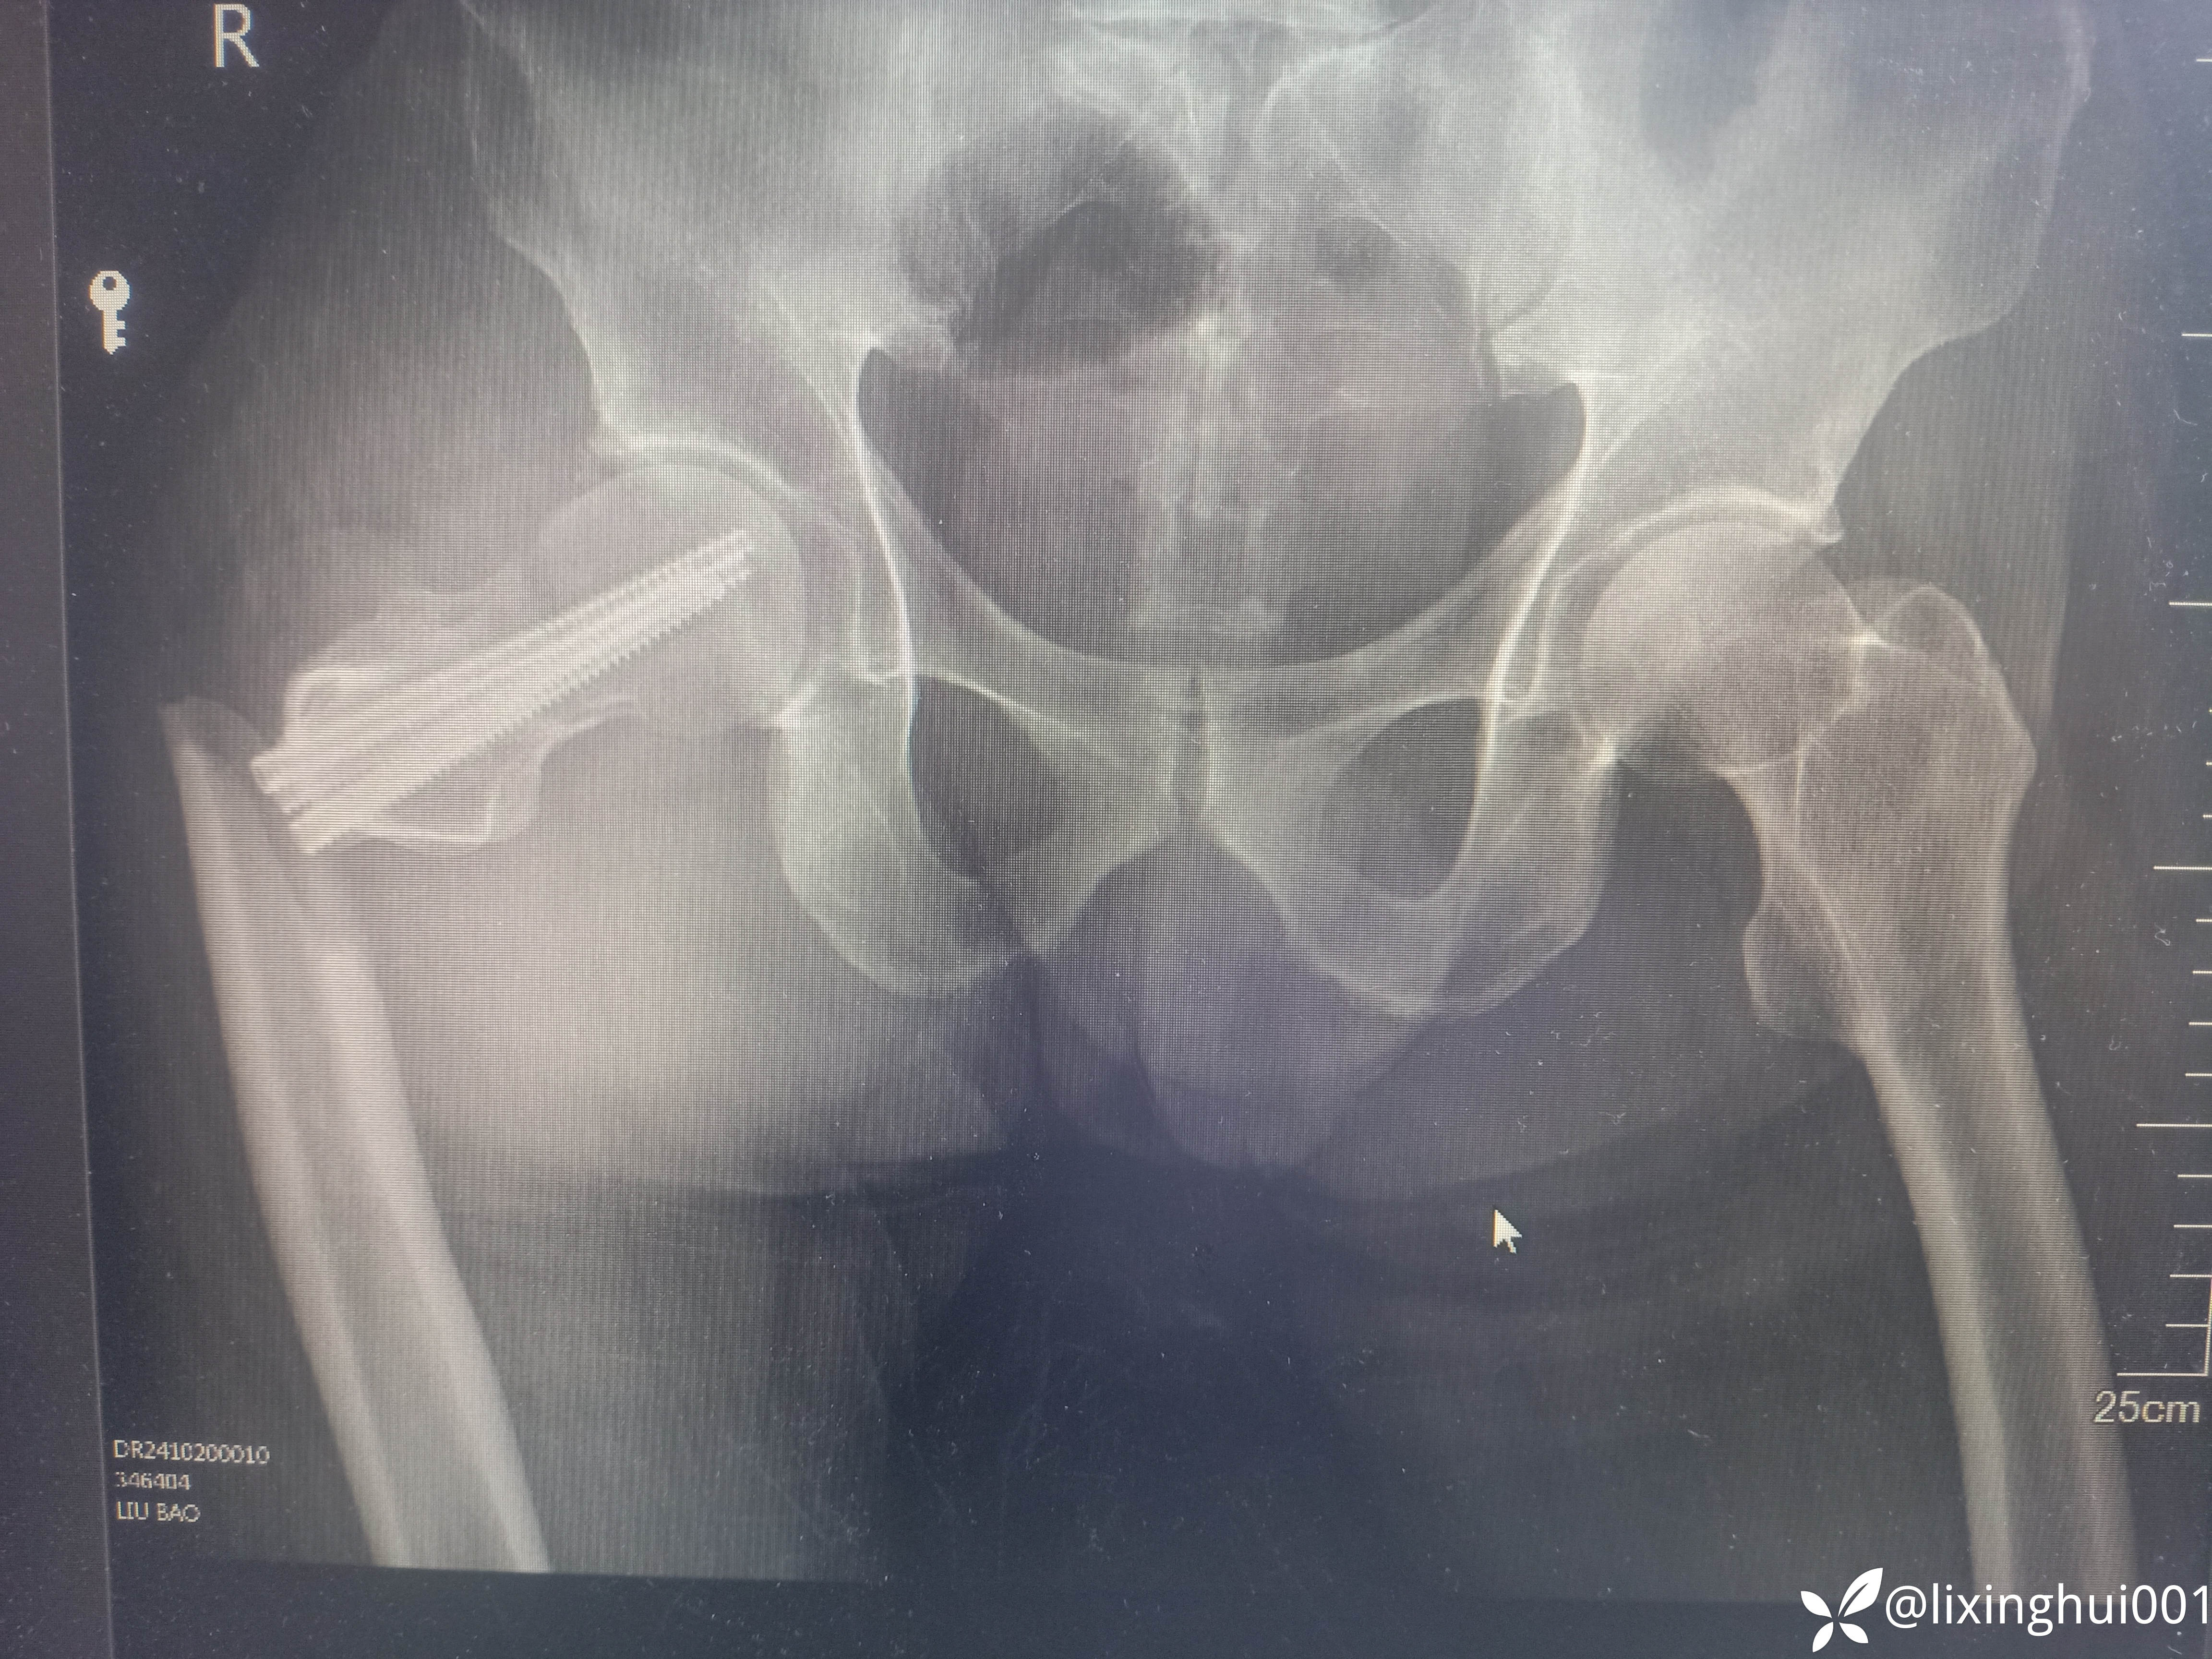

56岁股骨颈骨折术后股骨近端再次骨折

【患者信息】:56岁男性,40天前因右股骨颈骨折于外院行闭合复位螺钉内固定术,不慎再次摔伤来诊

【临床诊断】:右股骨颈骨折术后,→股骨近端骨折

【治疗经过及结果】:行切复内固定